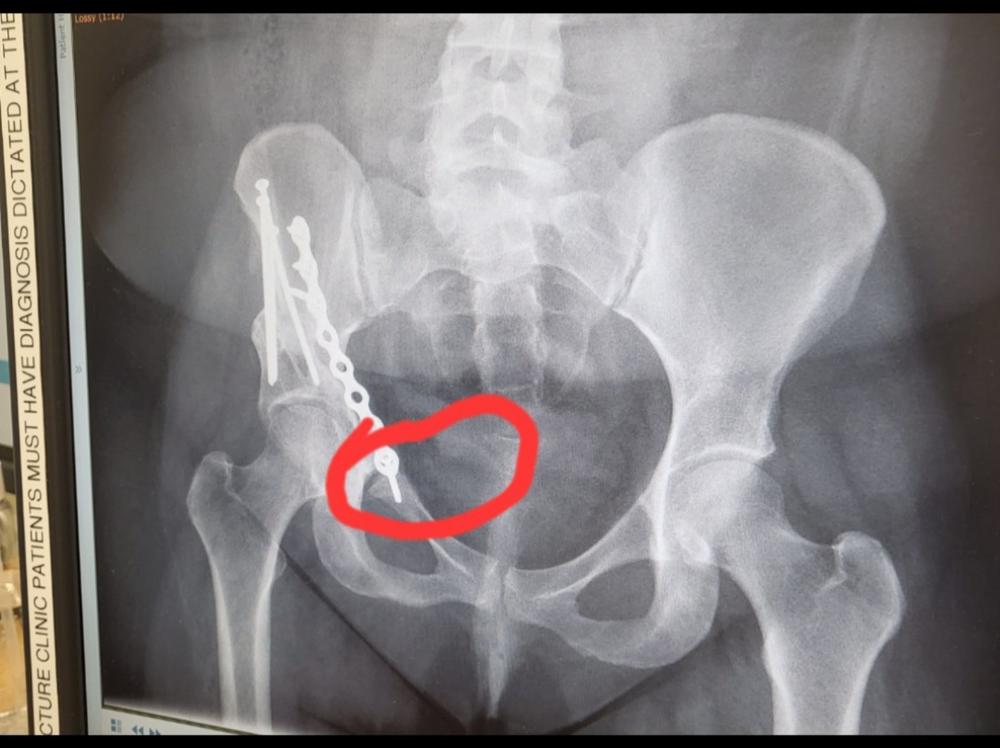

Hi my name is Vicky I'm 34 with 3 sons 14.10 an 7 who rely on me . I was in a car accident which torn my labrum then they found hip dysplasia so I'm not covered under acc I had pao surgery may 2021 which didn't heal at all so Feb 2022 had revision, bone graft and plate The plate is to short . The bottom part won't heal so I have a non union of the pubic ramus (broken pelvis) I woke up from surgery in agony the surgeon said oh that's probably the last screw we will remove it if it keeps causing pain then after about 6 months he said find another surgeon to fix you which their arnt any in the public sector in Newzealand. So I'm needing a mri in wellington

to see what is actually causing my pain . They don't know if it's the break or osteoarthritis or if the plate has damaged the psoas muscle I just know the pain is so so bad 24/7 and getting worse and the wait list for a mri is so long . I am currently under a public surgeon in masterton but he has no experience with someone with my complex pelvis/hip. Please can you help me get a mri so I can then try to get in with a private surgeon for a consult on what I can do . This pain is mentally and physically draining .